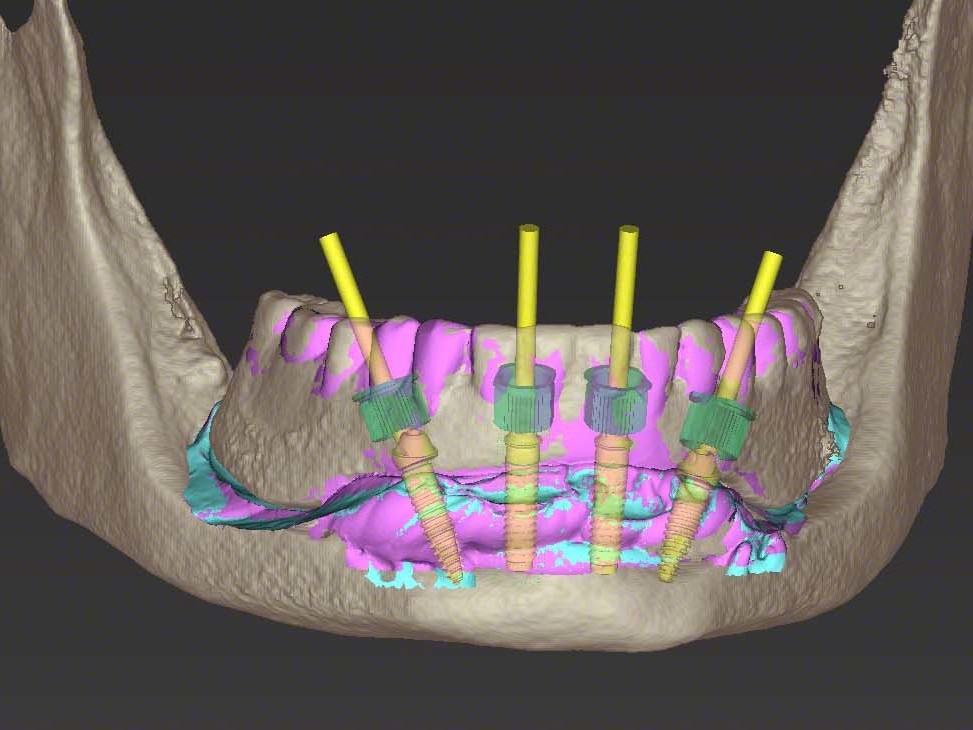

In dem vorgestellten Fall besitzen sowohl der MKG-Chirurg als auch das Dentallabor die coDiagnostiX Software. Der überweisende Zahnarzt kann über die kostenfreie coDiagnostiX App alle Planungsschritte mitverfolgen und ist so zu jedem Zeitpunkt optimal eingebunden. Die aus MKG-chirurgischer Sichtweise geplanten Implantatpositionen verifizierte der Zahntechniker im Dentallabor unter prothetischen Gesichtspunkten (Abb. 5). Zur besseren Visualisierung legte der Zahntechniker die zuvor erstellen digitalen Scans über das DVT. Die hochauflösenden Scans sind frei von Artefakten und geben dem Behandlungsteam somit detailliertere Informationen als das reine DVT. Der optische Scan der Bariumsulfatschiene auf dem Schleimhautmodell dient hierbei lediglich als Referenzierungspunkt für den Matchvorgang. Die beste Arbeitshilfe stellte der Scan der Schleimhautsituation dar. Mit diesem Scan wurde dem Zahntechniker die Auswahl der definitiven Abutments mit den richtigen Gingivahöhen enorm erleichtert. An den Positionen 32 und 42 wurde aus der coDiagnotiX Software die realistische Visualisierung zweier NNC Variobase-Klebeabutments geladen. Die distalen Implantatpositionen 35 und 45 wurden mit 30° verschraubten Sekundärteilen aus dem Pro Arch Konzept bedacht (Abb. 6, 7). Hierbei legte das Behandlungsteam besonderes Augenmerk auf eine prothetische Endsituation, die sowohl einer Steg- als auch Brückenversorgung gerecht wird. Nach Finalisierung der prothetischen wie chirurgischen Planung erfolgte das Design der Bohrschablone in der coDiagnostiX Software. Dem Anwender wird softwareseitig ein hohes Maß an Freiheit gegeben. Neben den verschiedenen Schablonenarten, die rein schleimhaut-, knochen- oder zahngetragen sind, besteht auch die Möglichkeit der Kombination als zahn-knochengetragene oder schleimhaut-knochengetragene Schablone. Darüber hinaus besteht eine Vielzahl an Hülsensystemen. Die Ausgabe der designten Bohrschablone und der prothetischen Planung erfolgte mittels Clickfee im standardisierten STL-Format. Die so gewonnenen Datensätze wurden zum einen in einer CAM-Software mit Supportstrukturen versehen und so für den stereolithographischen 3D-Druck vorbereitet und zum anderen in eine weitere CAD-Software geladen, mit der die provisorische Versorgung erstellt wurde.

Die coDiagnostiX Software ermöglicht seinen Anwendern die Ausgabe aller optischen Scans, der Implantatpositionen und der Abutments. Diese Informationen sind für viele implantologische Sofortversorgungskonzepte ausreichend. Im vorgestellten Fall wurden diese Daten jedoch um individuell erstellte Pro Arch Platzhalter ergänzt. Diese Pro Arch Platzhalter designte das zahntechnischen Labor in einer speziellen CAD-Software und simulierte so neben den realistischen Pro Arch Abutments auch deren provisorische Aufbauten. Darüber hinaus wurden sie mit einem Spacer versehen, der intraoperative Abweichungen der Implantatpositionen bis zu einem gewissen Grad toleriert. Der bereits in der Planungssoftware gematchte optische Scan der Bariumsulfatschiene gab dem Zahntechniker bei der Erstellung der provisorischen Versorgung die Ästhetik und Funktion vor. Die Implantatpositionen stammten aus der coDiagnostiX Planung und wurden um die eigens erstellten Pro Arch Platzhalter erweitert. Somit stellte der Zahntechniker sicher, dass alle relevanten Daten Beachtung fanden und ein vollkommen digitaler Workflow ohne Modelloperationen eingehalten werden konnte. Besonderes Augenmerk musste hierbei auf ausreichend dicke Wandstärken im Bereich der Pro Arch Platzhalter gerichtet werden, ohne dabei den Zungenraum zu sehr einzuschränken. Hierfür wurde ein spezieller flexibler PMMA-Kunststoff der Firma Zirkonzahn verwendet. Nach Fertigstellung des CAD-Designs erfolgte die Fertigung des digitalen Provisoriums auf einer Fünf-Achs-Simultan-Fräsmaschine. Anschließend wurden die vestibulären Gingivaanteile mit Nanocomposite verblendet.